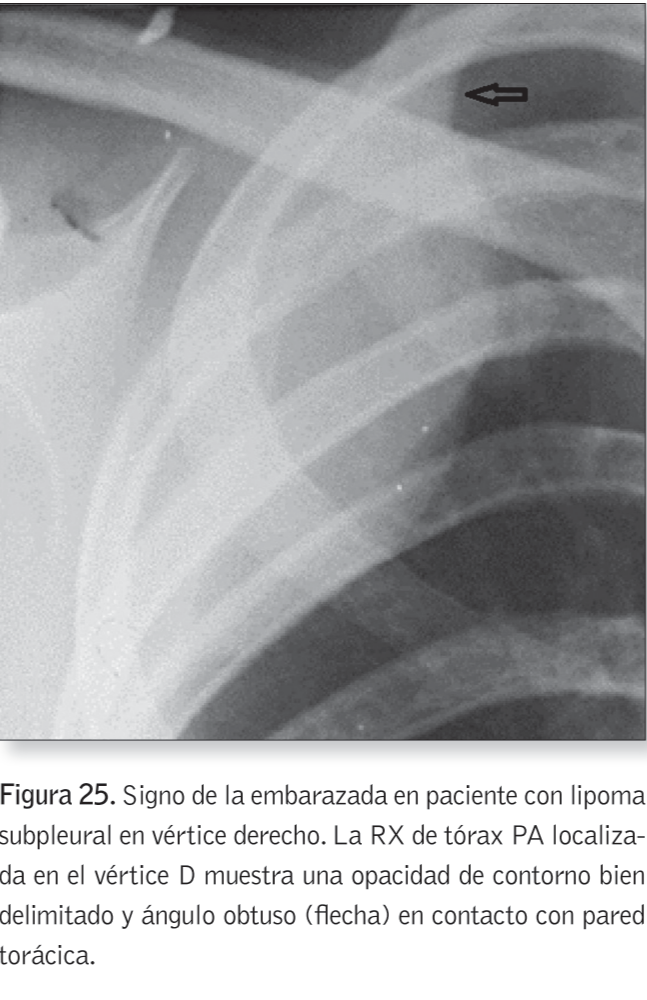

Signo de la embarazada